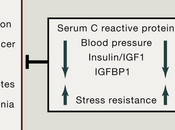

Anti-aging Interventions: from Elixirs to Fasting.

de Cabo et al. have done a useful review of different approaches to delaying or reversing aging, and I pass on their abstract and two nice summary graphics.... Read more